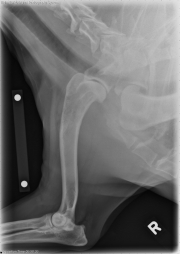

Today’s case is a 12-year-old female neutered Labrador Retriever with acute onset of lameness after chasing a ball. What is your diagnosis?

Right humerus: There is permeative lysis of the cranial and proximal diaphysis and metaphysis of the humerus. There is mild soft tissue swelling cranial to this region. Smooth periosteal reaction is visible on the caudal, medial, and lateral aspects of the humerus.

• Aggressive bone lesion in the right humerus, most likely a primary bone tumor

• Single pulmonary nodule, most likely metastatic disease.

Ultrasound fine needle aspirate of the humerus was performed. The cytological diagnosis was sarcoma, most likely osteosarcoma; however, hemangiosarcoma or histiocytic sarcoma could not be ruled out.